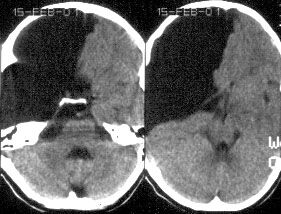

d. Аномалия Денди-Уокера (Dandy-Walker)

Агенезия червя мозжечка с формированием большой кисты ЗЧЯ, сообщающейся с 4-м желудочком, в результате атрезии отверстий Мажанди и Люшка. Следует четко дифференцировать это патологическое состояние от ретроцеребеллярных кист (последние редко требуют лечения и не связаны с 4-м желудочком).

Симптомы: гидроцефалия наблюдается у >90% больных с аномалией Дэнди-Уокера и, поэтому основными симптомами в раннем детском возрасте будут симптомы прогрессирующей гидроцефалии. Диагноз подтверждается путем проведения КТ или МРТ (предпочтительнее) головного мозга.